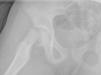

Presentamos el caso de una niña de 10 años (con antecedente de retraso de crecimiento intrauterino) en tratamiento con GHr a 0,035mg/kg/día desde hace 6 años, con una talla y un peso al inicio del tratamiento de 91,4cm (–3,33DE) y 12,4kg (–2,3DE); y actual de 136,2cm (–1,22DE) y 29,5kg (–1,15DE) (fig. 1), en seguimiento en traumatología por cojera y dolor en muslo derecho de 2 meses de evolución, que acude a urgencias por dolor súbito en ingle derecha y actitud en rotación externa de la pierna, objetivándose epifisiolisis grado I en el estudio radiológico. La familia decide esperar para intervención con enclavado profiláctico acudiendo días más tarde por aumento del dolor e impotencia funcional de dicha pierna con limitación para la rotación interna de la cadera. En la radiografía se objetiva epifisiolisis grado III (fig. 2) realizándose reducción y fijación con tornillos canulados (fig. 3).